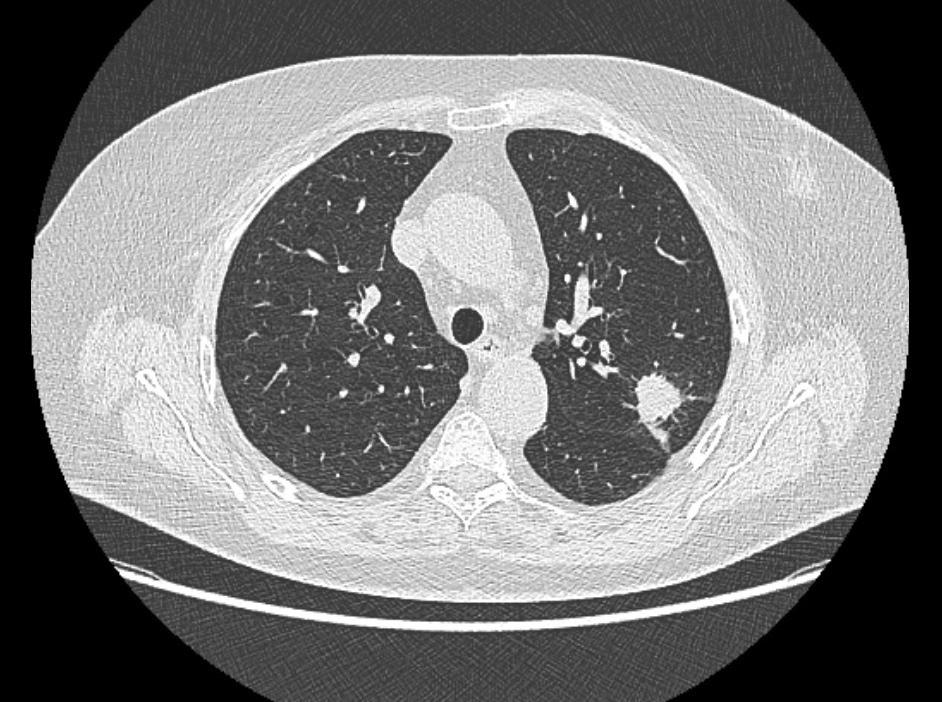

Aux États-Unis, des chercheurs de la faculté de médecine de l’université de Saint-Louis (Missouri) ont comparé les performances de radiologues et de l’intelligence artificielle dans la prédiction de la réponse au traitement du cancer du poumon. Ils ont réalisé une revue systématique et une méta-analyse, dont les résultats ont été publiés dans la revue Frontiers in Oncology au mois d’octobre. [1]

Pour leur étude, les chercheurs ont effectué une recherche systématique dans des bases de données telles que PubMed, Embase, Scopus, Web of Science et Cochrane Library depuis leur création jusqu'au 31 mars 2025. Au final, onze études rétrospectives ont été incluses dans l’analyse, couvrant l’évaluation de la réponse au traitement de 6 615 patients. « Les études incluses couvraient la période 2018-2024 et ont été menées aux États-Unis (n = 4), en Chine (n = 3), en Allemagne (n = 2), en Corée du Sud (n = 1) et au Japon (n = 1), précisent les auteurs. Les modalités d'imagerie co